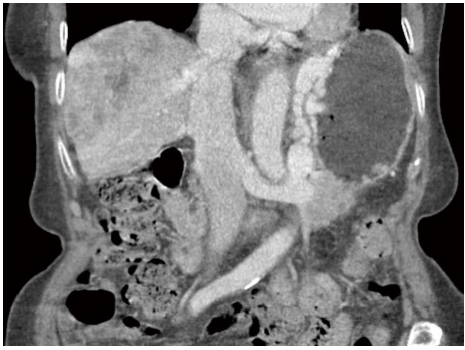

Mulher de 68 anos, com história de cirrose secundária a esteatohepatite não alcoólica, chega à emergência com quadro de vômitos em borra de café e fezes escurecidas nas últimas 48 horas, referindo ainda fraqueza e tonturas. Refere outro episódio semelhante no passado. Seu escore de Child é B (7 pontos), não apresenta história de encefalopatia ou ascite e sua hemoglobina é de 8g/dL. É realizada estabilização hemodinâmica com reposição volêmica seguida de endoscopia digestiva alta, na qual são observadas proeminentes varizes gástricas isoladas, com mucosa apresentando vergão vermelho e coágulos na cavidade, sem sangramento ativo no momento do exame. Uma angiotomografia venosa é realizada e está representada abaixo. Assinale a alternativa correta entre as abaixo.